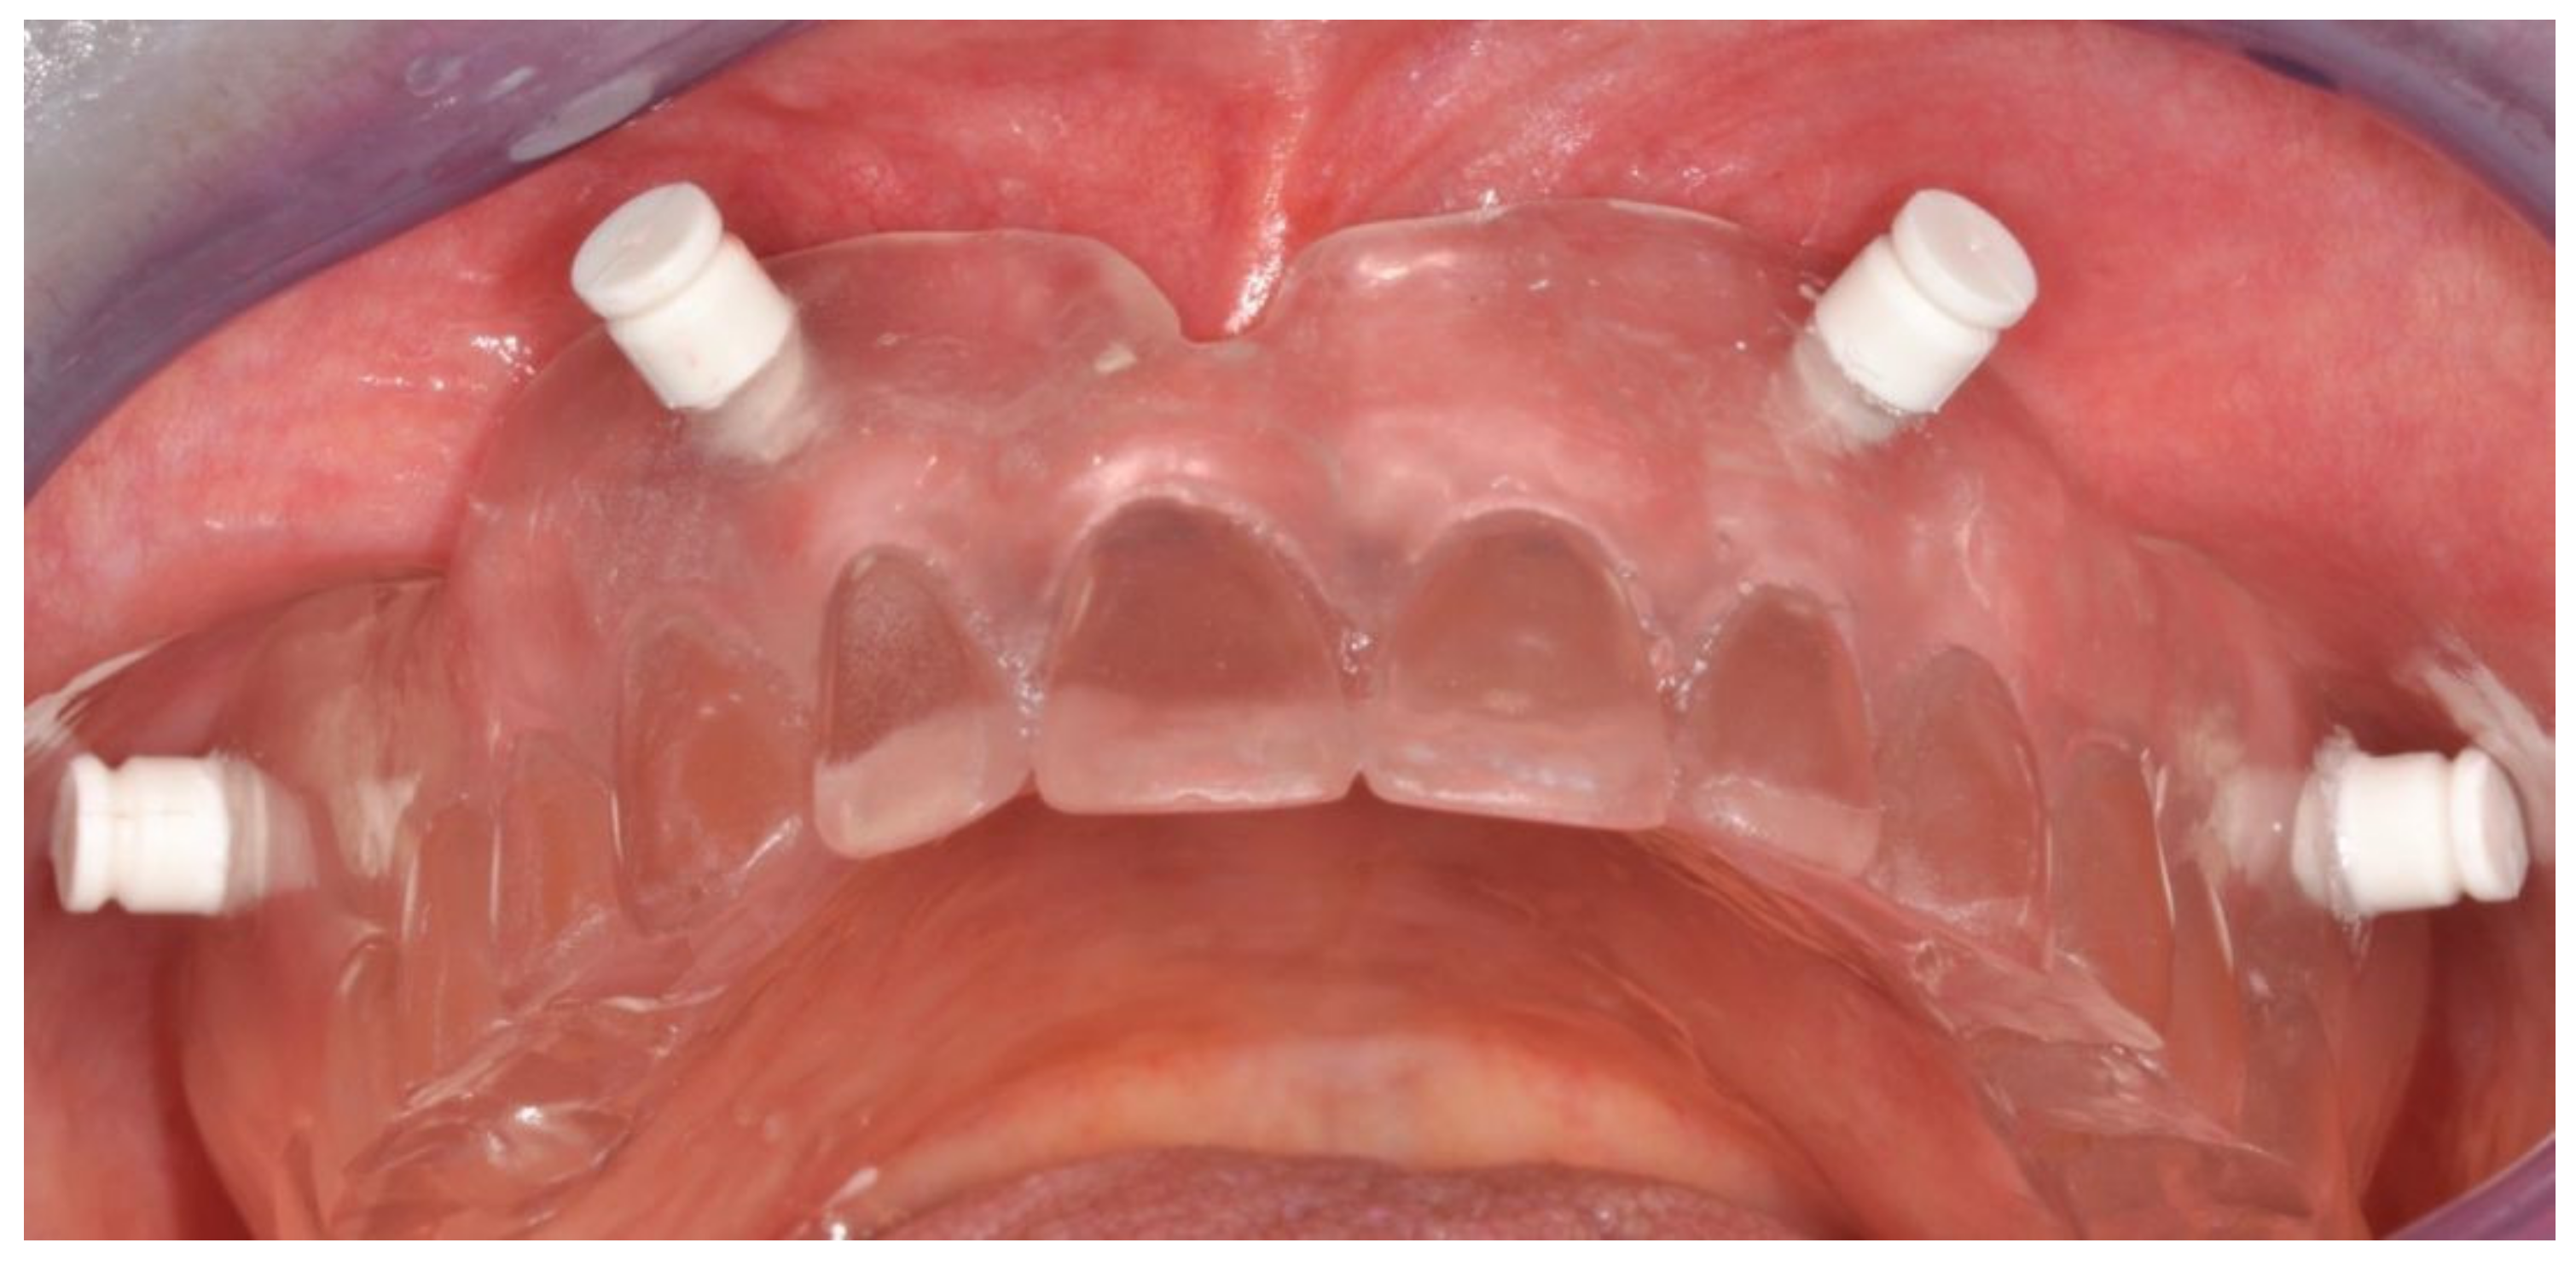

Figure 2.

Clinical view of an edentulous maxilla before treatment.